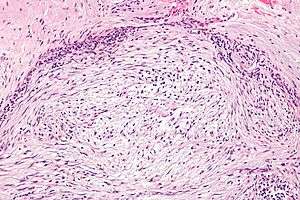

| Micrograph of nodular fasciitis showing the haphazard arrangement of cells (tissue culture-like pattern). H&E stain. | |

- Histologically vast array of patterns.

- Short S-shaped fascicles, inflammation, accelerated mitotic index with normal mitoses.

- Essentially spindle cell proliferation.

- Stroma is rich in collagen and/or myxoid ground substance.